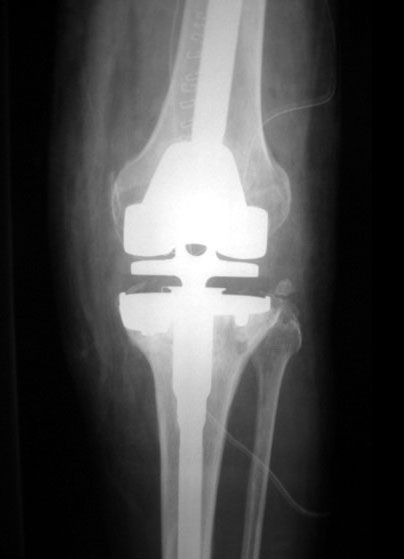

Revised TKR